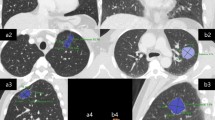

Descriptions of imaging features conform to the Nomenclature Committee of the Fleischner Society (NCFS) chest image definition [16]. All CT images were reviewed by the same two senior radiologists, who assessed and recorded lesion size and shape, single/multifocal lesion, halo sign, lobulation sign, spiculated sign, calcification, cavity, air bronchogram, the bronchovascular convergence sign, pleural indentation, pleural effusion, lymphadenectasis, distant metastasis and other signs (see Fig. 1 for definitions).

CT features. a The halo sign is a CT finding of ground-glass opacity surrounding a nodule or mass. b The spiculated sign is when the edge of a nodule or mass extends to the surrounding lung parenchyma, which contains linear strands that extend into the tissue of the lung but not into the pleural margin. c The lobulation sign is when the edge of the nodule shows uneven lobulated contour. d The cavity sign is a gas-filled space, seen as a lucency or low-attenuation area, within a pulmonary consolidation, mass, or nodule. e The calcification showed high attenuation, the average CT value of non-enhanced CT is >100 Hu. f The air bronchogram is a pattern of air-filled (low-attenuation) bronchi on a background of an opaque (high-attenuation) airless lung. g Pleural indentation is showed as a tapered or linear extension of the lesion to pleura, reflect the pulmonary fibrosis with adjacent pleural retraction. h The bronchovascular convergence sign is when one or more vessels reach the edge of the tumor or cross the tumor. i Lymphadenectasis means the size of a mediastinal or hilar lymph node is >1 cm in short axis diameter